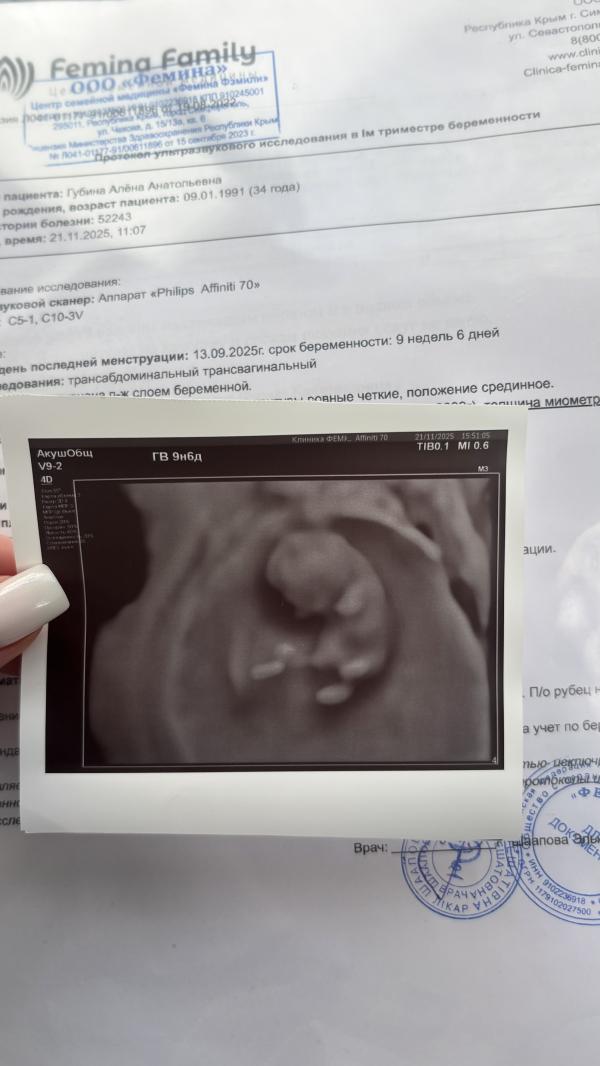

По месячным 9 недель и 6 дней вчера было, сделали узи и я в шоке была от того какой малыш уже. Он двигается там во всю, он живой и это уже не просто набор клеток, а выглядит уже как малюсенький человечек. У него есть ручки и ножки, их хорошо видно 🥲 Так приятно было увидеть его, познакомится с ним, кажется только вчера я, не полностью, но на процентов 50 осознала, что внутри меня растет малыш. До этого не было вообще осознания. После вчерашнего узи я уже начала принимать этот факт, стало как-то проще.

И кстати, если вдруг вы сейчас +- на моем сроке то ваш ребетенок выглядит вот так 🙂👇🏼